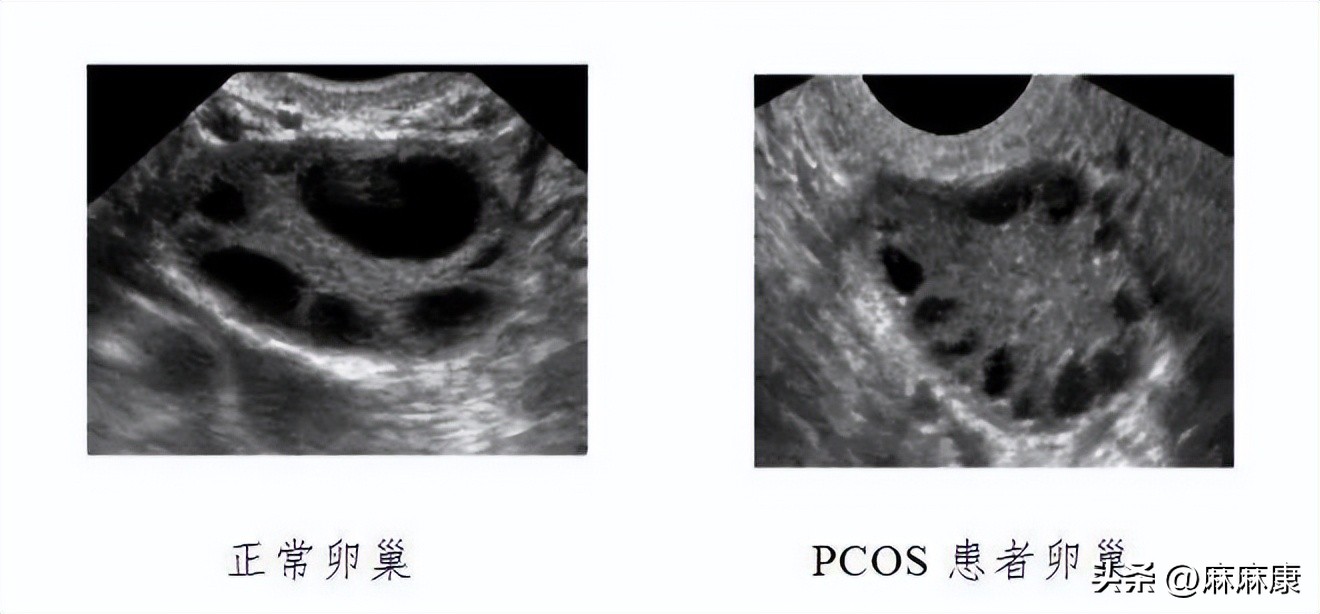

三、超声提示:卵巢多囊性改变。

一侧或两侧卵巢各有12个及以上直径为2-9mm卵泡,呈车轮状排列,称为“项链征”。连续监测未见主导卵泡发育及排卵迹象。